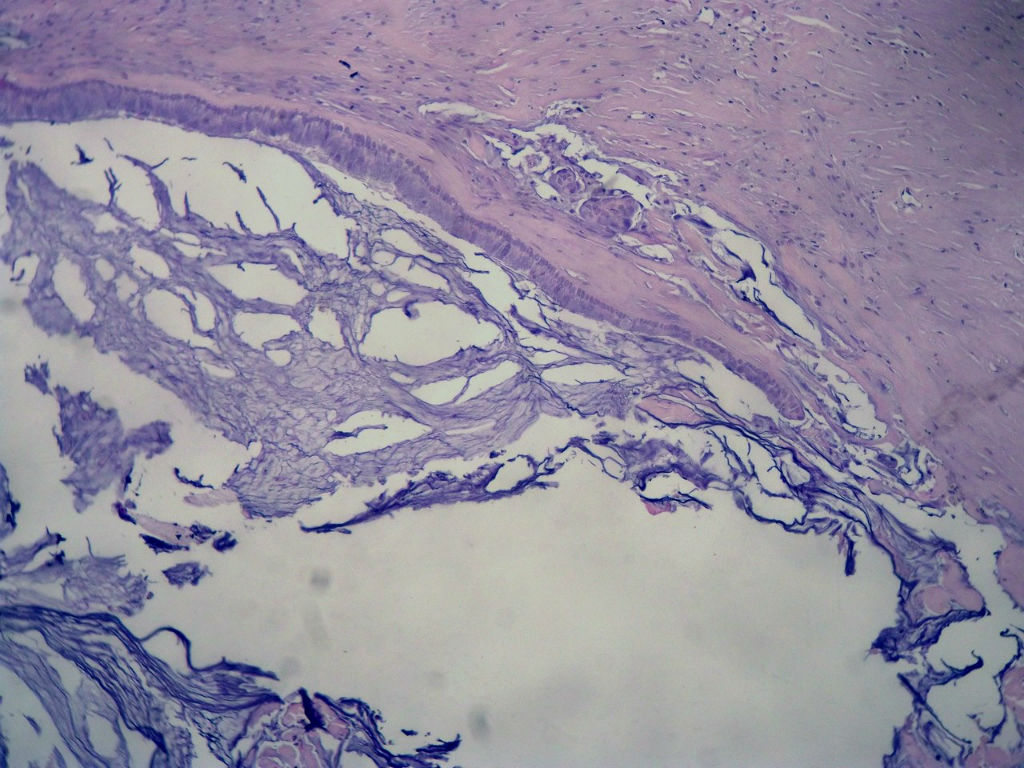

• 女,80岁,阑尾区肿块。图3

图3

送检为不规则组织多块,粘滑,解剖结构辨认不清。术中探查双侧卵巢无异常。

阑尾粘液性肿瘤,癌的可能性大

粘液长在肌层,而且漂浮着可疑上皮细胞,最大可能粘液腺癌。